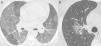

Nonenhanced high-resolution chest CT of different patients with confirmed COVID-19 pneumonia and typical findings. A, 74-year-old man presented with 7-day history of fever and cough. Axial CT shows multifocal, peripheral and rounded ground glass opacities (GGO). B, 47-year-old man presented with 10-day history of moderate breathlessness and fever. Axial CT shows reversed halo sign. C, 70-year-old woman presented with 9-day history of mild dyspnea and COVID-19 exposure. Axial CT shows GGO with a perilobular pattern. D, 36-year-old man presented with 5-day history of fever, cough and myalgia. Axial CT shows bilateral areas of crazy-paving pattern.

Commonly typical features reported in COVID-19 pneumonia were multifocal, rounded and peripheral GGO displaying a sensitivity of 95.3% (95%CI 88.5-98.7), 82.5% (95%CI 72.8-89.9) and 81.7% (95%CI 71.6-89.3), respectively (Table 2; Fig. 3). All patients with atypical appearance (n = 17) on chest CT were not diagnosed with COVID-19 by RT-PCR. Of these, according to their attendant physician, 13 had the final diagnosis of bacterial pneumonia, one had decompensated heart failure and three had no confirmed alternative diagnosis. The most common findings among these patients were centrilobular nodules (n = 15) and tree-in-bud opacities (n = 7) (Fig. 4). Among patients with indeterminate appearance (n = 30), seven had a positive RT-PCR for SARS-CoV-2. In this group, common findings were very few and non-rounded GGO (n = 4), diffuse GGO (n = 2), and unilateral features (n = 1) (Fig. 5). One of them also had radiological features of pulmonary fibrosis.